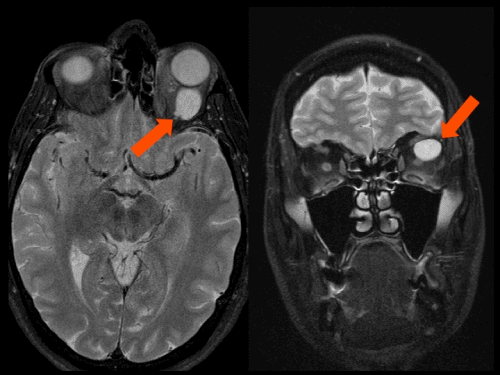

Son necesarias pruebas de imagen como la resonancia magnética nuclear (RMN) o la tomografía computerizada (TAC) o escáner para obtener más información sobre las características del tumor y su localización. En la mayoría de los casos será necesario realizar una biopsia para llegar a un diagnóstico.

Tumor órbita

¿Cómo saber si un tumor de órbita es benigno o maligno?